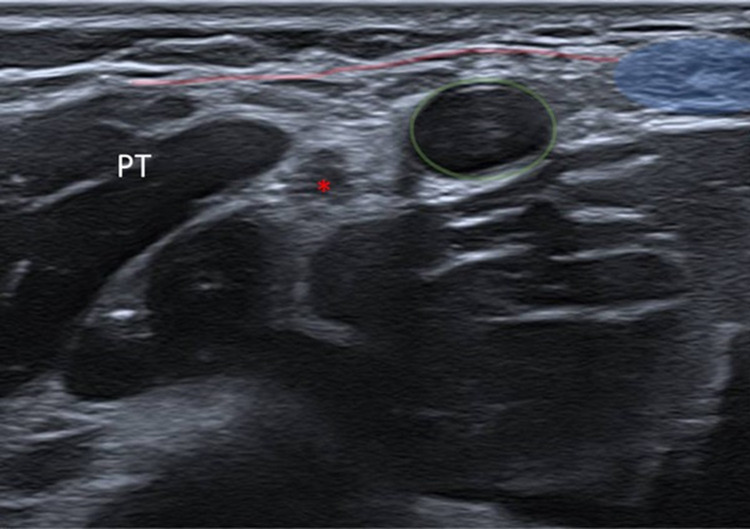

Background: The lacertus fibrosus serves as a site of entrapment for the proximal median nerve. Traditionally, surgical intervention has been the preferred method for resolution. This study demonstrates that perineural corticosteroid injection of the proximal median nerve entrapment under ultrasound guidance can improve nerve compression, strength, and pain in patients with lacertus fibrosus syndrome (LFS).

Methods: A retrospective quasi-experimental cohort study without a control group following the STROBE guidelines was conducted from July 2020 to May 2023. The patient selection was carried out considering Elisabet Hagert's diagnostic criteria. Ultrasound-guided proximal perineural corticosteroid injections were administered in the region of the lacertus fibrosus. Contingency tables were constructed to compare pre-and post-intervention data. The McNemar test was performed to evaluate the differences. Odds ratios (with 95% CI) were calculated to estimate the likelihood of improvement. A level of less than 0.05 was considered statistically significant. All analyses were performed using the R program.